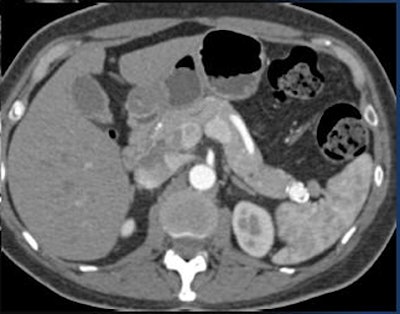

Metastatic tumors of the pancreas, particularly renal cancers, are especially vascular on arterial-phase imaging, but these, too, quickly become isodense, he said.

![]() |

| A renal cell carcinoma metastasis to the pancreas is seen only on arterial-phase CT. |